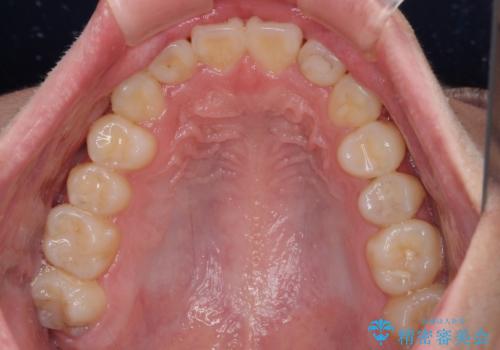

- 八重歯を気にして来院された高校生の患者様です。

ボディーコンタクトの激しい部活動を行っているため、補助装置とインビザラインを用いて、部活動を継続しながら治療を行うこととしました。

八重歯を効率よく改善するため、補助装置を使用して上顎の奥歯を後方に移動させました。

部活動をしながらでしたが、マウスピースをしっかりと装着してくださったので、1年半程度で終了することができました。